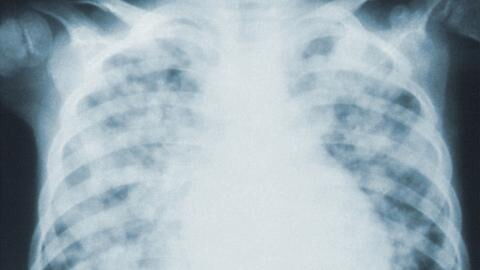

There are fears that tuberculosis (TB) is on the rise due to people assuming they have Covid and cases going undiagnosed during the pandemic. It’s important to consider TB when symptoms and risk factors for the disease are present. But what are the symptoms and how are they different to Covid?

According to WHO, TB and Covid are both infectious diseases that attack primarily the lungs. Both diseases have similar symptoms such as cough, fever, and shortness of breath or difficulty breathing. However, TB has a longer incubation period with a slower onset of disease.